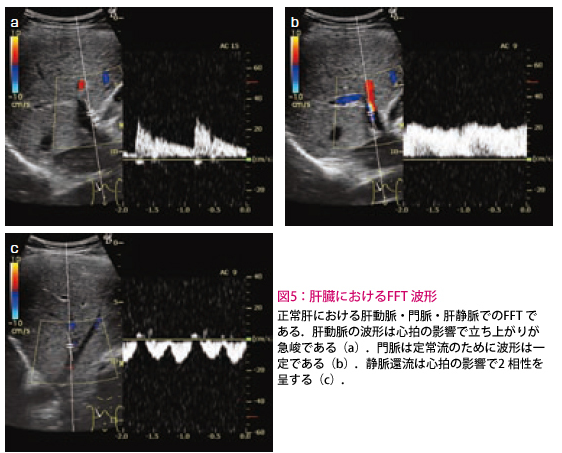

パルスドプラ法(PWD)では、Bモード上にサンプルボリューム(SV)のカーソルが表示され、その横に血流波形(FFT波形)が示されます。

SVはBモード上の自由な部位に設定できます。FFT波形の表示では、縦軸が流速で横軸が時間を表しています。基線の上側に表示されるのはプローブに向かってくる流速で、逆に下側に表示されるのはプローブから遠ざかる流速を意味します。このようにパルスドプラ法では、断層像を見ながら自由に目的部位の血流観察を行うことができます。サンプルボリューム内(=の形の中)の血流情報を解析する場合に用いる

FFT波形の種類には、山と谷が周期的に現れる拍動流波形と平坦な定常流波形(図5b)の2つがあります。拍動波は立ち上がりが急峻で速度の速い動脈波形(図5a)と、流速が低く2相性を示す静脈波形(図5c)に分かれます。このことからFFT波形の特徴を理解すれば、その血管が何であるかを知ること(動脈・静脈・門脈の判別)ができます(図5)。

流速の速い動脈のFFT波形では、折り返し現象がしばしば経験されます(図6)。折り返し現象とは、測定範囲を超えた速度部分が反対側に表示されることです。この折り返し現象を解消するには2つの方法があります。(1)「ゼロシフト」ボタンで基線を動かして表示範囲を移動させる方法と、(2)「流速調整」ボタンで最高流速の値を変化させて表示範囲の縮尺を変える方法です。